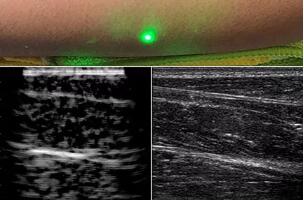

臨床應(yīng)用的無創(chuàng)超聲,要求探頭與人體皮膚直接接觸來向身體傳導(dǎo)高頻振動(dòng)的超聲波。但是,有一些特定的患者卻在超聲檢查時(shí)受到限制,比如兒童、燒傷患者和敏感皮膚患者等。而近日麻省理工學(xué)院的研究人員證明,確實(shí)有可能使用激光在不接觸皮膚的前提下對(duì)患者進(jìn)行超聲波掃描。

而麻省理工學(xué)院的研究小組現(xiàn)在開發(fā)了一種使用激光檢測皮膚上超聲波振動(dòng)的方法,以便可以使用一種激光使皮膚產(chǎn)生共振,而另一種則可以檢測到振動(dòng),從而達(dá)到“遠(yuǎn)程超聲掃描”的作用。

目前,研究人員已經(jīng)與健康的志愿者測試了他們的系統(tǒng):從半米遠(yuǎn)處掃描了他們的前臂,并將這些結(jié)果與傳統(tǒng)超聲的結(jié)果進(jìn)行了比較。他們能夠觀察到深達(dá)6厘米的組織,并能看到肌肉,脂肪和骨頭,并報(bào)告其結(jié)果可與標(biāo)準(zhǔn)超聲相媲美。

研究人員用一種激光裝置測試了這個(gè)想法,該裝置使用一個(gè)波長為1,550納米的脈沖激光來產(chǎn)生聲波,并使用第二個(gè)連續(xù)激光,調(diào)諧到相同的波長以遠(yuǎn)程檢測反射的聲波。第二個(gè)激光器是靈敏的運(yùn)動(dòng)檢測器,可測量聲波從肌肉,脂肪和其他組織反射回來而引起的皮膚表面振動(dòng)。反射的聲波產(chǎn)生的皮膚表面運(yùn)動(dòng)會(huì)導(dǎo)致激光頻率發(fā)生變化,這種變化可以測量。通過機(jī)械掃描人體上的激光,科學(xué)家可以獲取不同位置的數(shù)據(jù)并生成該區(qū)域的圖像。